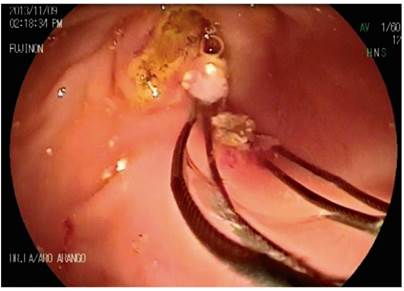

Primary pancreatic duct stones smaller than 5 mm are managed with standard ERCP maneuvers for stone removal (Figures 7, 8, 9, 10). Stones larger than 5 mm require the use electrohydraulic, extracorporeal, or Spyglass-guided electrohydraulic lithotripsy. In the latter case, the duct can be entered for use of a laser to fragment stones. 29 We have been gaining experience with the use of a cholangioscope which has been very useful for non-surgical management of patients with pancreatic stones. Figures 11, 12 and 13 show the Spyglass inside the Wirsung duct performing laser lithotripsy on a large stone. After the procedure, a pancreas stent is always placed.

Figure 11 Calculi within the Wirsung duct seen by cholangioscopy (image courtesy of Unión de Cirujanos SAS, Manizales, Colombia).

Figure 12 Calculus fragments fractured by laser and ready to be extracted (image courtesy of Unión de Cirujanos SAS, Manizales, Colombia).